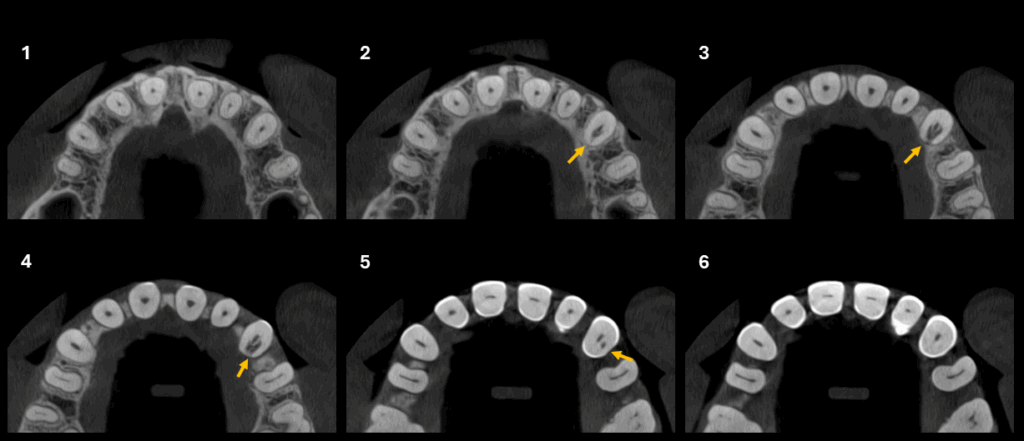

CORTES AXIALES

En la tomografía computarizada de haz cónico se identifica en la pieza 23 una imagen isodensa que compromete las paredes radiculares mesial, distal y palatina a nivel del tercio cervical, en estrecha proximidad con el conducto radicular. Asimismo, se observa un ensanchamiento del espacio del ligamento periodontal adyacente.

- Reabsorción cervical externa en pieza 23.